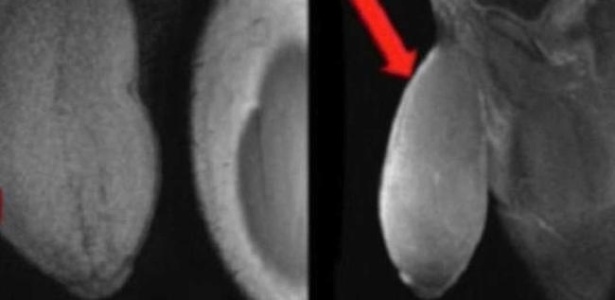

O pênis do jovem tinha um formato incomum, como de uma bola de futebol americano, segundo o médico Rafael Carrion (Foto: Reprodução/Journal of Sexual Medicene)

À imprensa, o médico descreveu o órgão sexual do jovem como um bola de futebol americano, com quase 18 centímetros de comprimento, quando flácido, e quase 26 centímetros de circunferência.